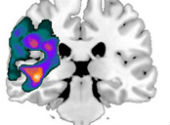

Acest studiu, sponsorizat de către Stroke Association (Asociaţia pentru Accidente vasculare cerebrale) şi condus în parteneriat cu universităţile Manchester şi Bangor, este cel mai mare studiu de neuroimagistică asupra afaziei Wernicke. Cercetătorii au rugat 12 persoane cu afazie Wernicke şi 12 subiecţi control să realizeze corelaţii logice între nişte imagini şi cuvinte în timp ce erau monitorizaţi neuroimagistic. Scanarea neuroimagistică a înregistrat zonele de la nivelul creierului care erau irigate cu sânge şi care regiuni cerebrale răspundeau în urma acestei sarcini.

Rezultatele au fost surprinzătoare. Deşi persoanele cu afazie Wernicke erau considerate a fi profund afectate, cercetătorii au descoperit că, în cazul lor, creierele răspundeau mai mult decât cele ale persoanelor neafectate. Ceea ce este important, multe dintre aceste răspunsuri neurale intensificate au fost localizate într-o zonă a creierului responsabilă de recunoaşterea obiectelor, oamenilor, cuvintelor şi a faptelor.

Rezultatele nu au fost cum ne aşteptam. Toţi participanţii noştri cu afazie de tip Wernicke au prezentat mai multă activitate cerebrală decât grupul control. În mod surprinzător, aceste modificări au avut loc la nivelul creierului în zone cunoscute ca lobii temporali anteriori despre care se crede că facilitează sau „înmagazinează” cunoştinţele conceptuale. Deşi aceste persoane prezintă tulburări de înţelegere, reuşesc în mod clar să acceseze centrul cunoştinţelor conceptuale, în anumite cazuri bazându-se mai mult pe acest centru al cunoştinţelor conceptuale decât persoanele care nu prezintă afazie de tip Wernicke. Îşi solicită sistemul mai mult pentru a realiza aceeaşi sarcină.”